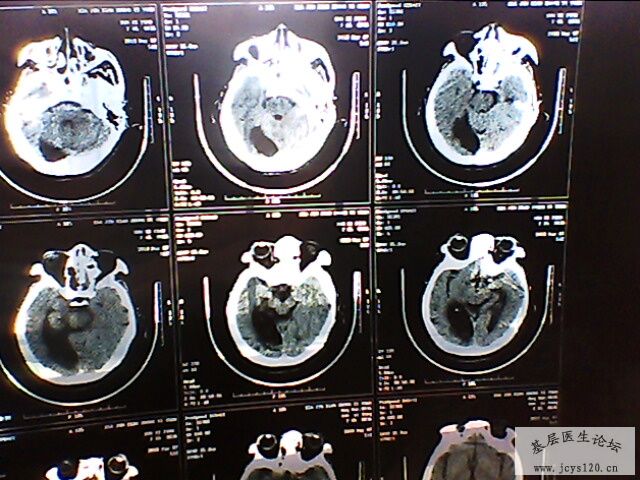

右侧肢体活动障碍半小时

患者,女,65岁,在半夜起来上厕所时发现右侧肢体不能活动,无头痛,无恶心呕吐,无意识障碍,无大小便失禁,持续大概十分钟后症状消失,唯感觉右侧肢体稍无力,为进一步检查和治疗来诊。

查体:血压160/90 mmHg 心率80次/分

自主体位,神志清楚,语言流利,双侧瞳孔等大等圆,对光反射灵敏,伸舌居中,心肺听诊、腹部检查无异常,四肢活动正常,肌力正常,病理征未引出,生理反射存在。

既往史:既往体健,三天前在家因为头晕测血压200/100mmHg ,在家口服药物(复方利血平)后血压降至正常。无心脑血管疾病病史。